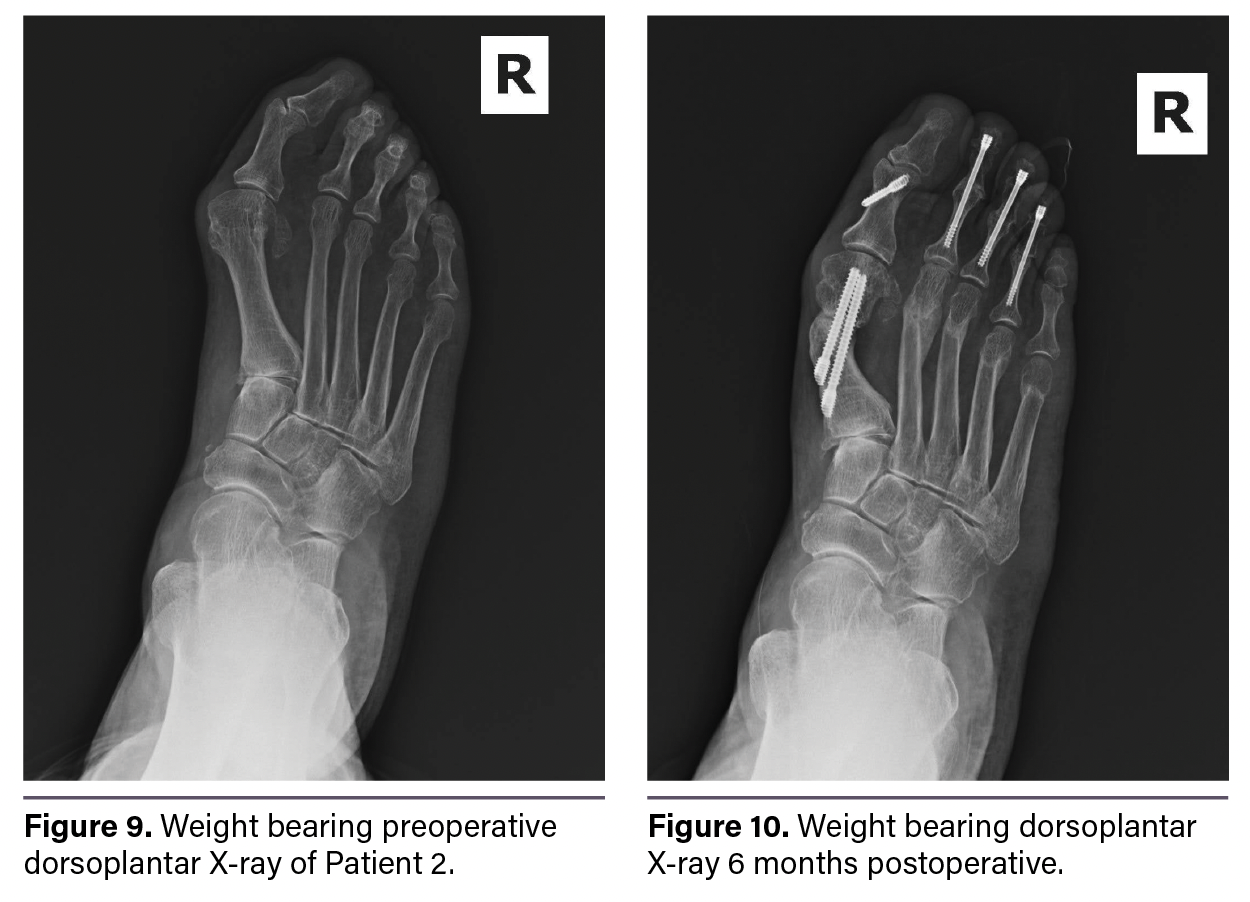

Figure 9 shows a preoperative weight-bearing dorsoplantar X-ray. Figure 10 shows a 6-month postoperative weight-bearing dorsoplantar X-ray. Figure 11 shows a preoperative weight-bearing lateral X-ray. Figure 12 shows a 6-month postoperative weight-bearing lateral X-ray reflecting healing. The patient’s hallux angle was 13 degrees compared to 35.4 degrees preoperatively. The first IMA was 2.2 degrees with a tibial sesamoid position of 3 compared to preop values of 16.3 degrees and 6, respectively. The fourth–fifth IMA was 2.3 degrees compared to 8.3 preoperatively.